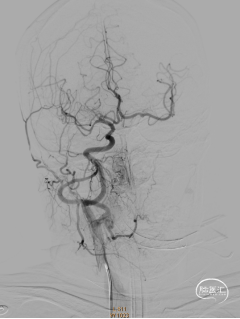

通过6F抽吸导管应用50ml注射器负压抽吸出大量暗红色血栓后,造影可见左侧颈内动脉后交通段显影。

再次应用6F抽吸导管抽吸,仍有少量暗红色血栓抽出,造影可见左侧大脑前动脉及左侧大脑中动脉。大脑动脉M1远段未见显影(血栓逃逸)。